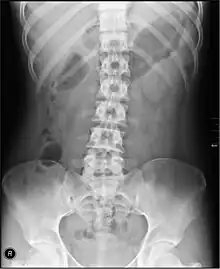

Une radiographie de l'abdomen sans préparation.

Radiographie de l'abdomen sans préparation

La radiographie de l'abdomen sans préparation, plus souvent abrégé « Abdomen sans préparation » (ASP) ou abdomen à blanc consiste à radiographier l'abdomen sans produit de contraste, contrairement au transit baryté ou au lavement baryté.